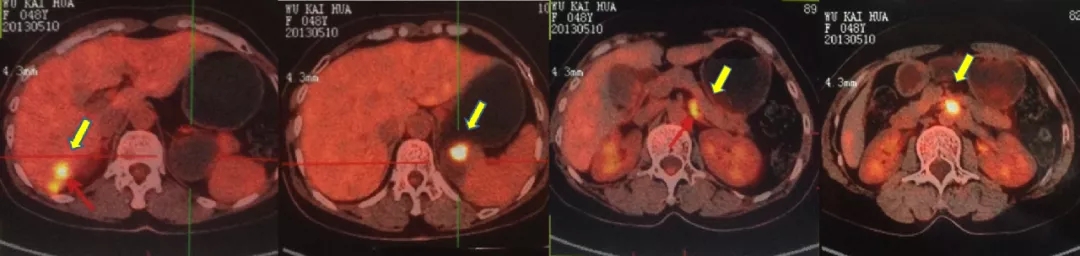

2013.5.10 PET-CT:肝肾隐窝、脾肾间隙、脾门旁、腹膜后可见斑片状、囊实性及结节状影,实质部分FDG代谢增高,考虑转移。

2013.5.10 PET-CT检查结果